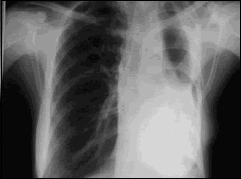

- Neumonectomía y lobectomía: extirpación de un pulmón completo o de un lóbulo pulmonar, respectivamente.